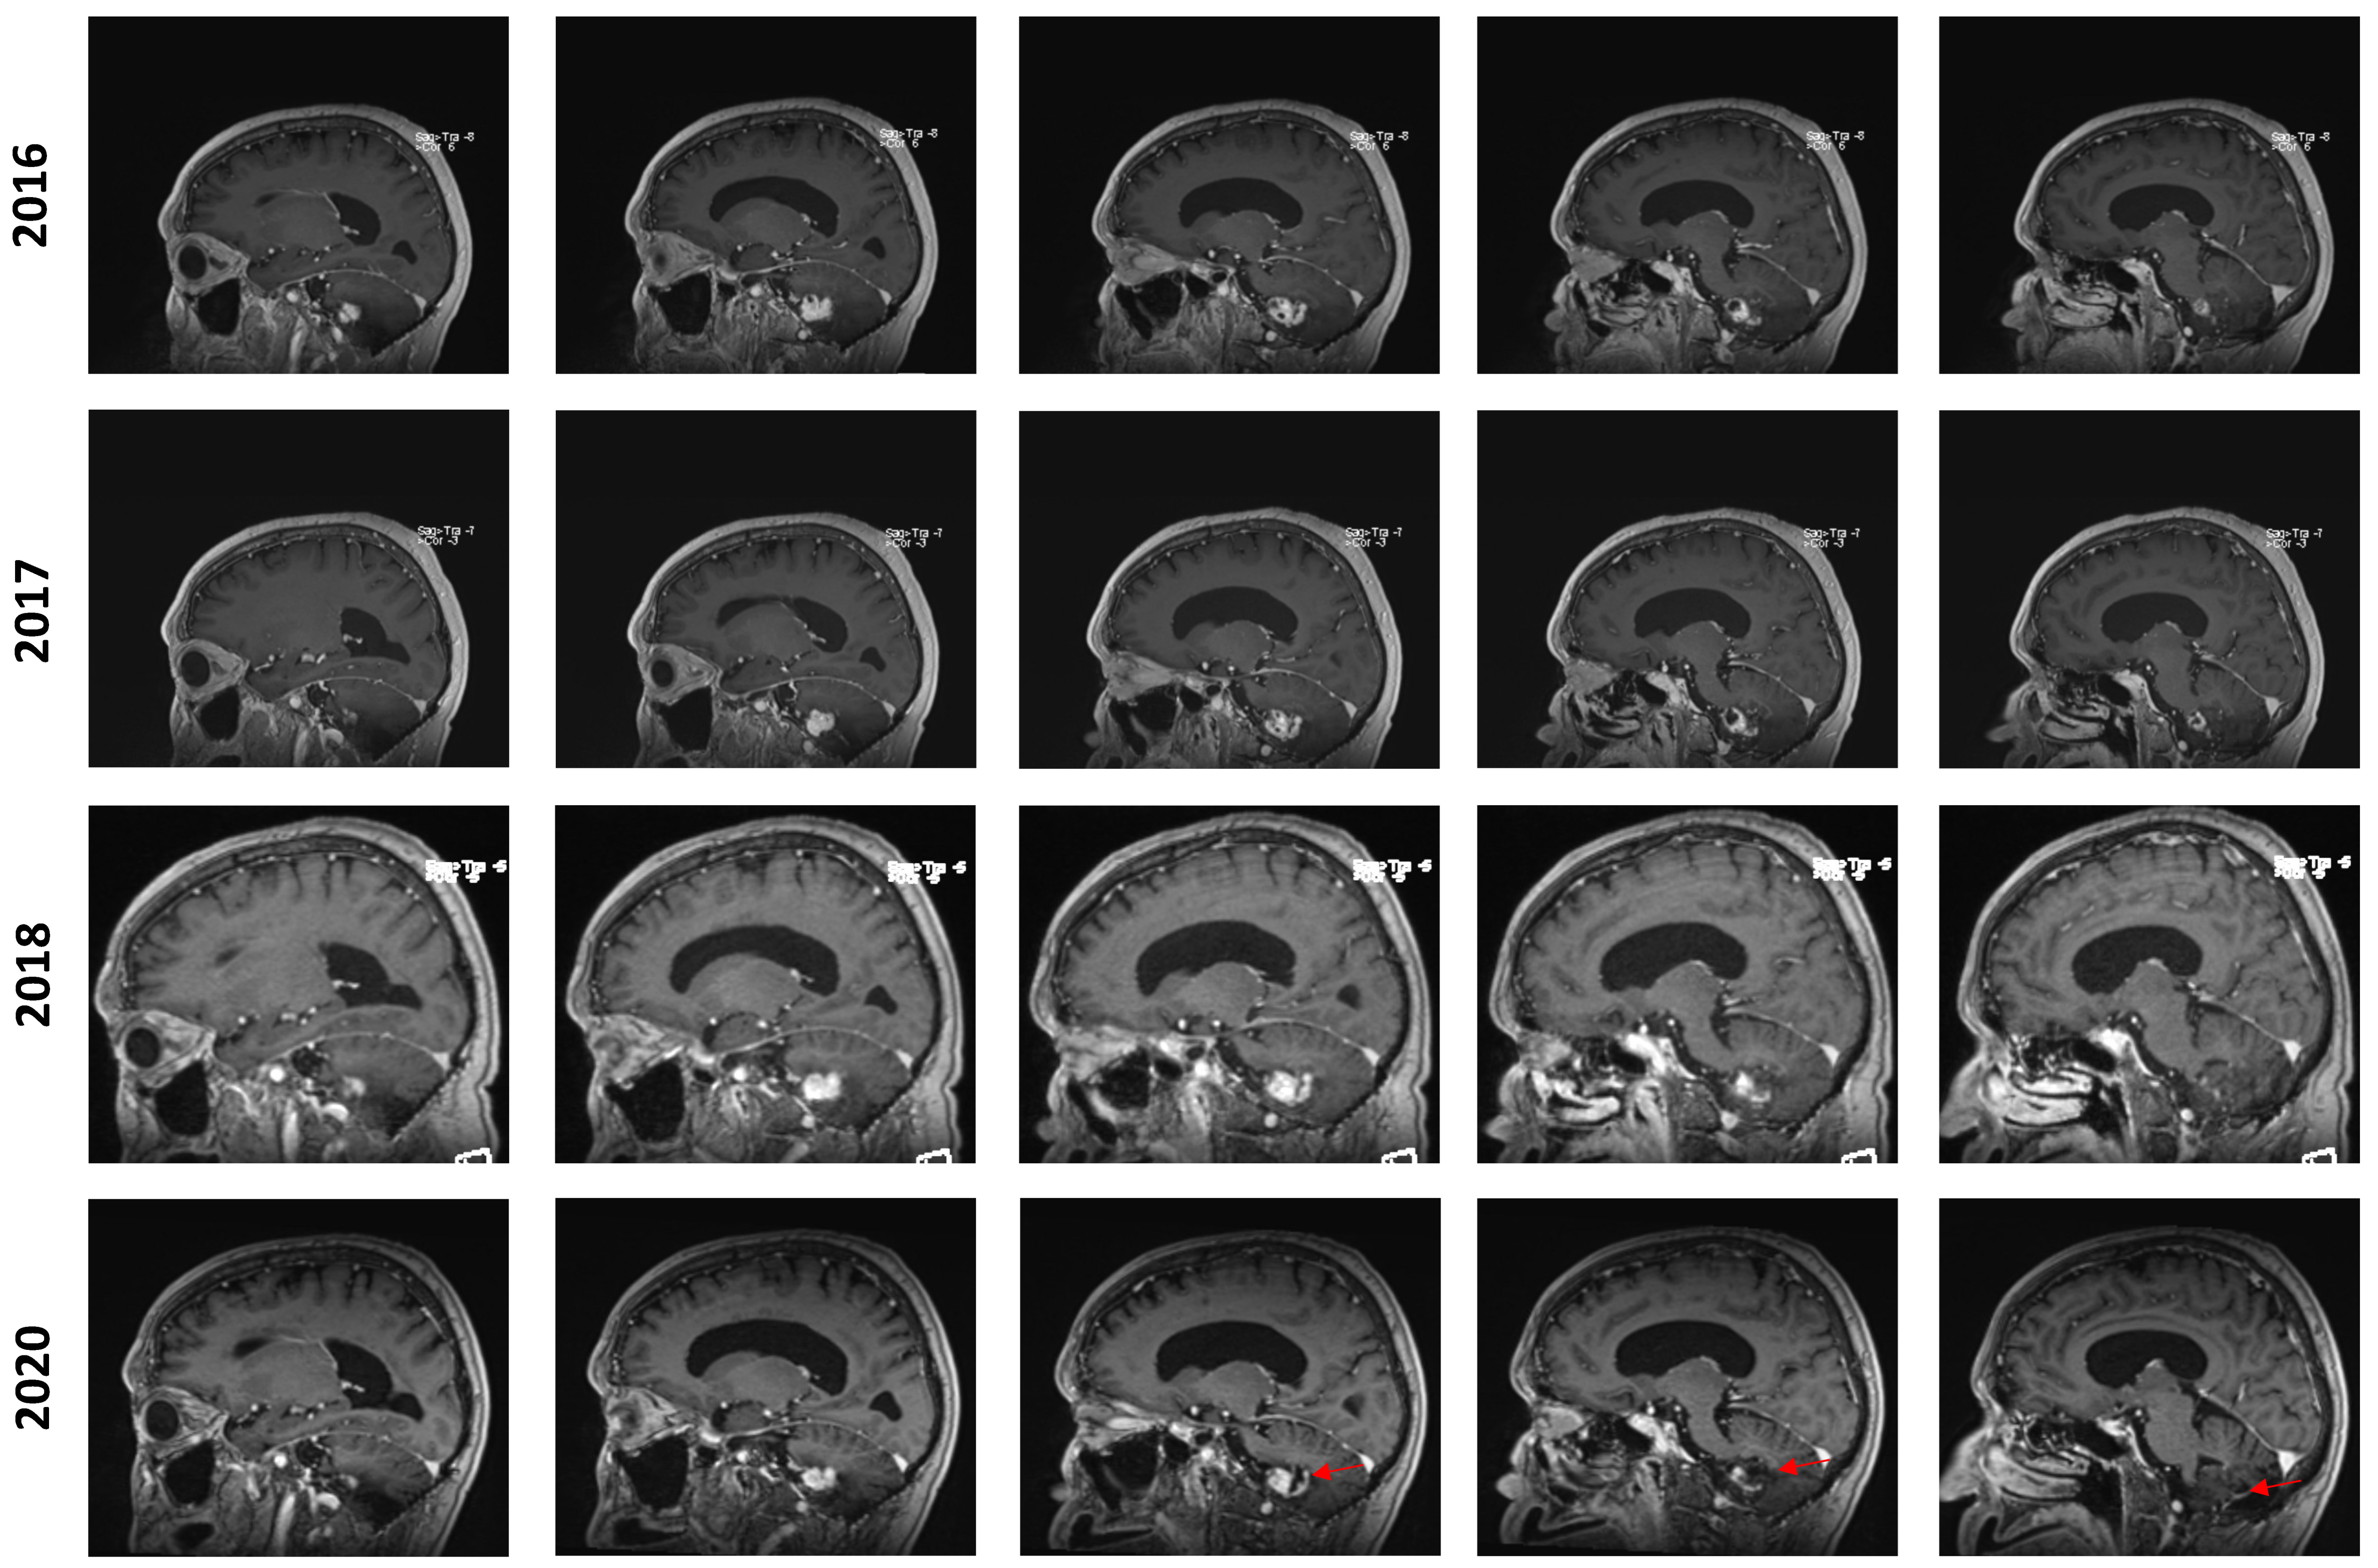

In February 2022, at the age of 72 years old, the patient was hospitalized in his hometown following the appearance of symptoms and was referred to neurosurgery. He mainly displayed loss of balance, unexplained loss of weight, confusion, and psychomotor retardation. He was able to ambulate without the aid of a walker, albeit at a very slow pace. Dexamethasone failed to improve his condition. An MRI underlined a right-sided, cerebellar intra-axial lesion located at the anterolateral portion of the cerebellar hemisphere. The lesion, determined to be a relapse of the initial HBL, displayed a nodular component in intimate proximity with the brainstem, measuring 36.2 × 32.1 × 31.9 mm (Figure 3). The presence of two cystic components were also noted. The first, located posteriorly, measured 32 mm maximally (Figure 4, blue marker). The second, located antero-infero-medially, measured 21 mm maximally and protruded in the subarachnoid space at the level of the pons (Figure 4, pink marker). The lesions caused a mass effect on the medulla, the inferior aspect of the pons, the middle cerebellar peduncle, and at the level of the 4th ventricle with associated hydrocephalus.

Figure 3. Pre-surgical MRI of the lesion. Representative capture of the T1-weighted MRI pre-surgical imaging. Representative measurements are color-coded. (A) Sagittal images are organized left to right and represent a left–right progression in the sagittal plane. (B) Coronal images are organized left to right and represent a posterior-to-anterior progression in the coronal plane.